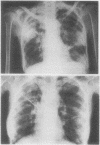

The first reported case of pulmonary infection with Nocardia caviae in Britain occurred in a 67 year old woman, in whom diabetes mellitus and liver cirrhosis probably contributed to impaired cell mediated immunity. She was successfully treated with gentamicin 60 mg eight hourly and sulphadimidine 500 mg six hourly for six months and then with sulphadimidine 2 g/day for a further three months. When Nocardia caviae is isolated from the sputum of a patient with chronic respiratory infection and fever, effective treatment should be started promptly.

Images in this article